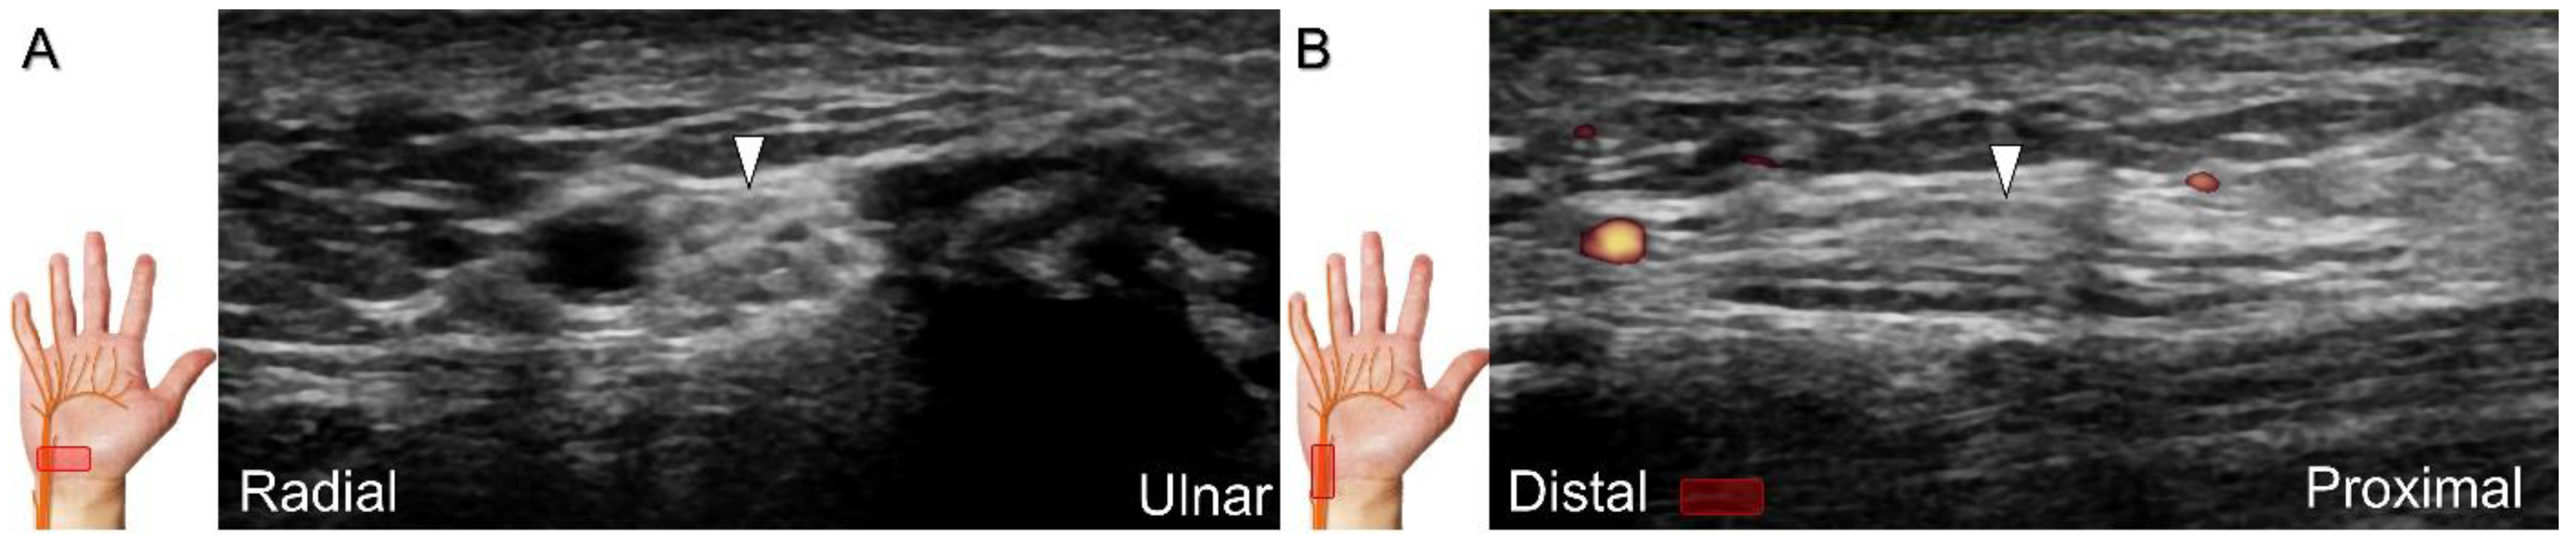

Injuries to the dorsal common digital nerve typically occur in the workplace as a result of cutting or crushing. However, the nerve can also sustain damage due to various other factors such as fracture, ganglia, tenosynovitis, tumor (Figure 34), foreign objects, or boxing, which may cause contusion over the first knuckles (Figure 35).

US imaging may reveal a neuroma in cases where patients report chronic allodynia and/or tingling sensation in the affected digit (Figure 36). To perform hydrodissection, the in-plane approach can be utilized in the nerve’s short axis after identifying the extensor digitorum tendons and the dorsal metacarpal arteries (Figure 37).

Figure 36. Sonographic imaging (short-axis view) for a neuroma of the dorsal common digital nerve, proximal site (A) and the site of the lesion (B). Long-axis imaging of the nerve/neuroma (C). White arrowhead: normal dorsal common digital nerve; black arrowheads: neuroma. SB: sagittal band; E: extensor tendon; MCP: metacarpal bone; DIO: dorsal interosseous muscle; A: artery.